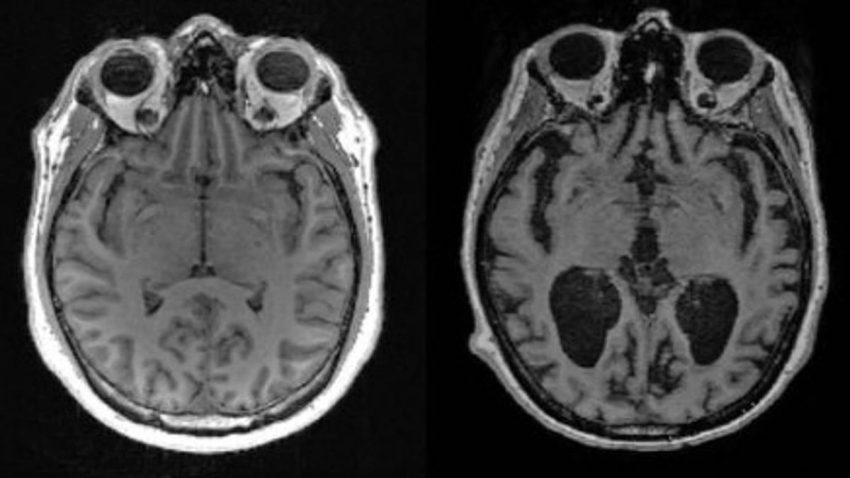

Científicos de la Facultad de Medicina de Harvard descubrieron que la pérdida de litio en el cerebro humano es uno de los primeros cambios que conducen al Alzheimer, mientras que en ratones, una depleción similar de litio aceleraba el deterioro de la memoria.

El análisis reveló que el litio era el único metal con niveles marcadamente diferentes entre los grupos, que además parecían cambiar en las fases más tempranas de la pérdida de memoria.